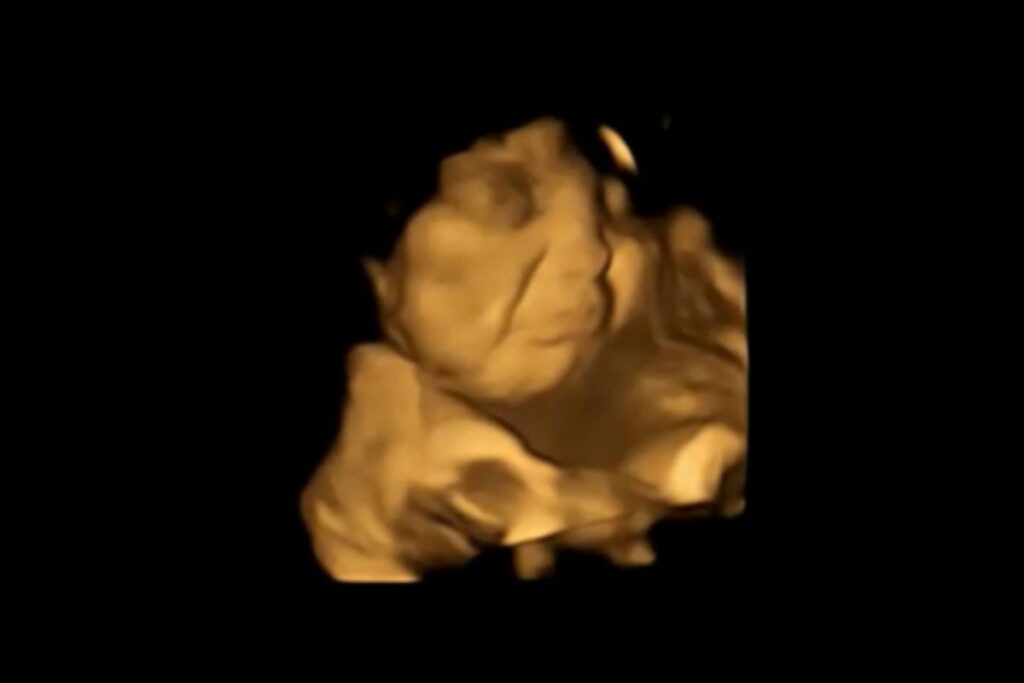

Já os pequenos que sentiam o sabor de couve acabavam fazendo uma careta. Parecia, até mesmo, que eles iam chorar. Confira!